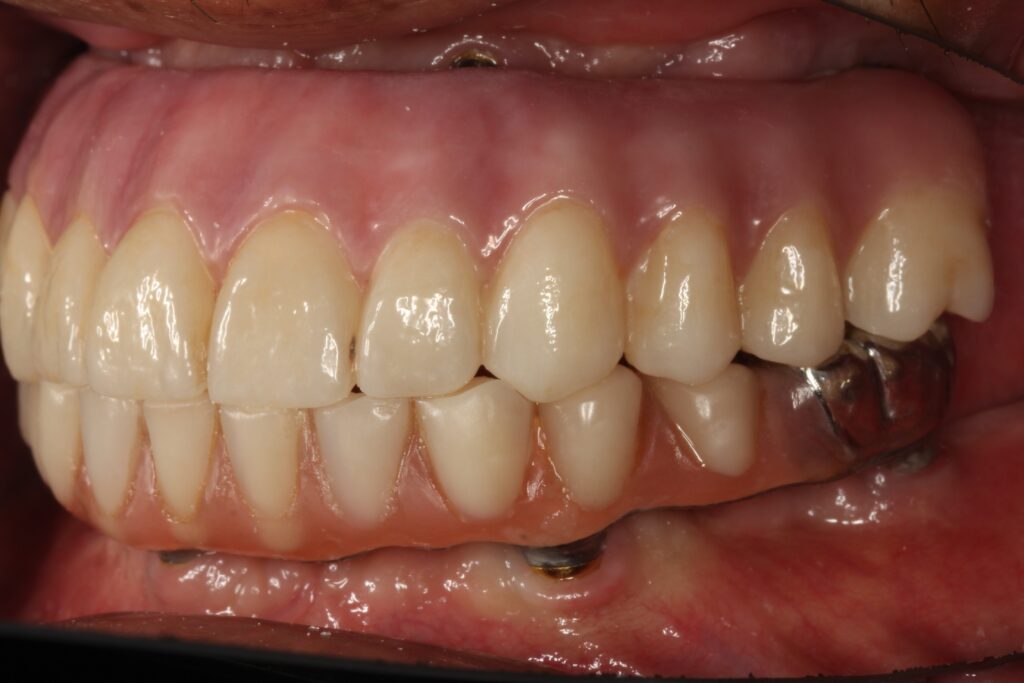

A selection of full arch fixed implant bridge patients after 5 years of wear

Oral Surgeons – Dr Han Choi, Dr Sam Goldsmith, Dr Rajiv Rajpal NSOMS

Prosthodontist – Dr Alan Payne NSOMS/Northland Prosthodontics

Dental technicians – Hosaka Takashi, DT Denture Design, Auckland, CJ Park, Project Dentistry, Auckland and Osteon Medical, Melbourne, Australia.